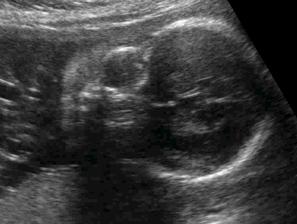

Testy + utz + bříško ♥